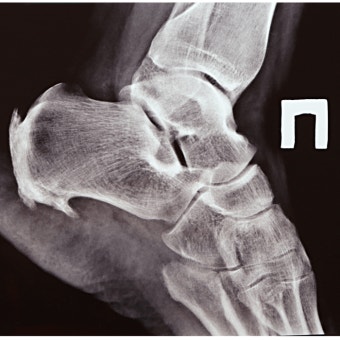

3. 엑스레이(X-ray) 검사

발뼈 튀어나옴 진단의 핵심은 엑스레이 촬영입니다. 특히 **체중을 실은 상태(Weight-bearing X-ray)**로 촬영하는 것이 중요합니다. 이 검사는 다음과 같은 정보를 제공합니다:

- 엄지발가락과 제1중족골 간의 각도(Hallux valgus angle)

- 뼈 돌출의 정도

- 관절 간격의 변화

- 연골 상태

엑스레이 결과를 통해 무지외반증의 진행 단계를 확인하고, 수술이 필요한지 여부도 판단할 수 있습니다.